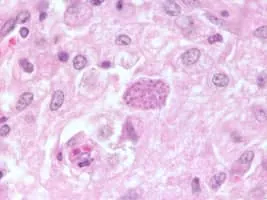

Neospora photograph

Neospora is a single celled parasite of livestock and companion animals. It was not discovered until 1984 in Norway, where it was found in dogs. Neosporosis, the disease that affects cattle and companion animals, has a worldwide distribution. Neosporosis causes abortions in cattle and paralysis in companion animals.